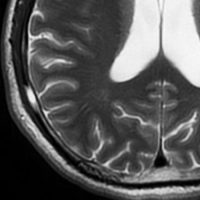

51歳の男性にみられたものです。脳ドックをきっかけにみつかりました。何もないところから発生して増大してまた3ヶ月くらいで消失していきます。左上から1月間隔くらいのMRIです。

もちろん生検手術などしません。

ガドリニウム像です。極期を過ぎているのでリング状増強で,これも縮小消失していきます。